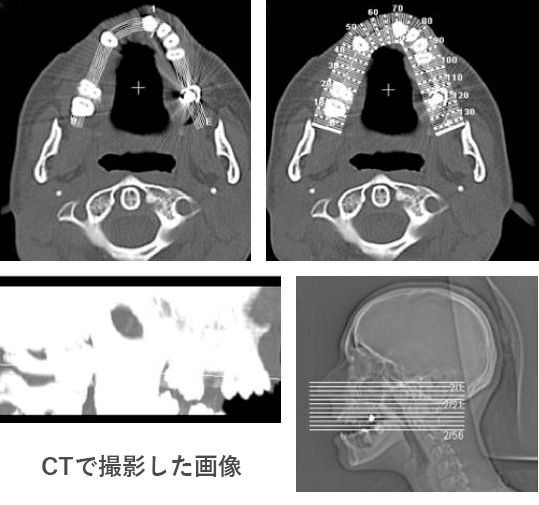

CT(Computed Tomography)とは、CT撮影装置とコンピューター処理により画像の再構築を行い、断層写真が得られる装置のことです。

CTを使用することで、レントゲンでは見えなかった部分を確認出来るようになり、骨の厚みや密度などの詳細な計測が出来るようになり、より安全で高度な治療が可能になります。